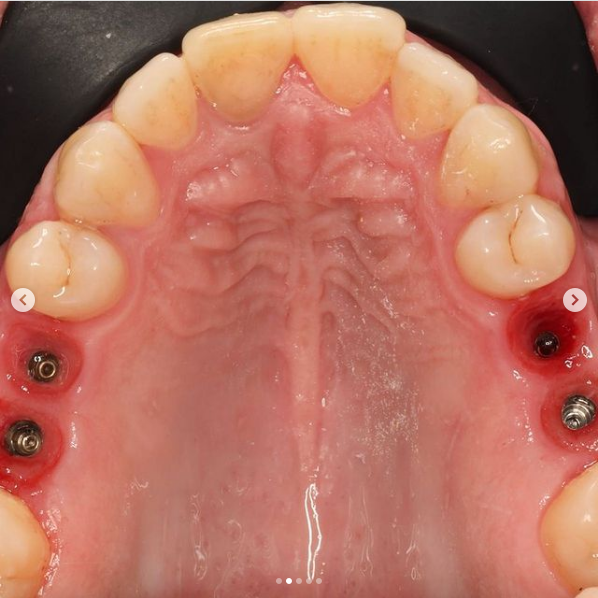

2 работы в портфолио

Магомедов Гамзат Абдулбариевич принимает в Клинике KRAFTWAY (КРАФТВЭЙ) в Москве. Стаж 20 лет. Специализируется на ортопедии, по которой клиника оказывает 8 услуг. Имеет 2 работы до/после в портфолио. Квалификация специалиста подтверждена 9 лицензиями, сертификатами и наградами. Для уточнения дополнительной информации о специалисте или записи на прием можно позвонить по телефону

Сфера практических интересов: - Сложные ортопедические реабилитации, - Протезирование с опорои? на имплантатах, - Эстетические керамические реставрации (виниры, вкладки, накладки), - Несъемное и съемное протезирование,? - Диагностика и лечение мышечно-суставных дисфункции?. Постоянно проходит обучение по данным направлениям в стоматологии.